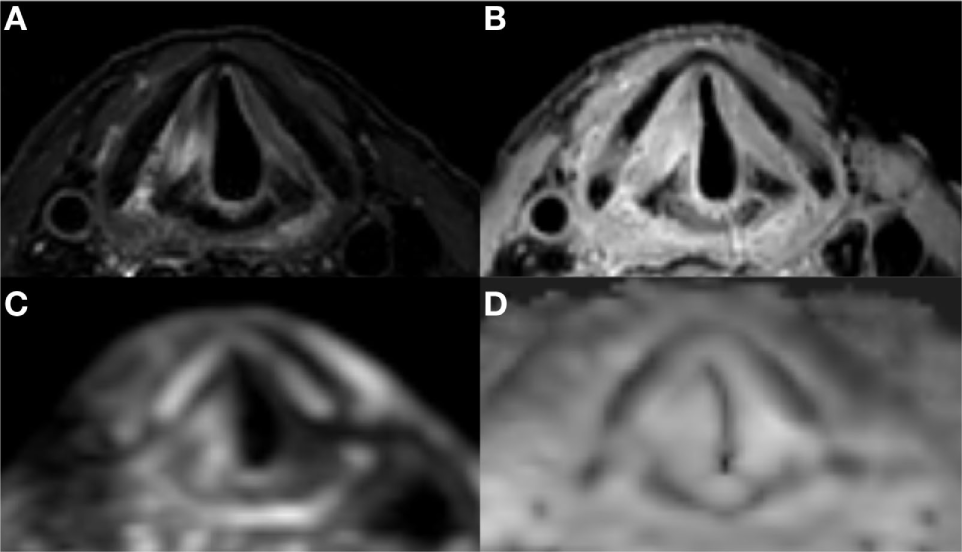

Figure 7

Laryngeal magnetic resonance imaging of a patient with superficial recurrence after radiotherapy of an early glottis carcinoma: high signal intensity in the right vocal cord and posterior paraglottic space on T2 (A) combined with a high signal intensity on both DWI (C) and ADC (D) is compatible with post irradiation edema and rules out deep tumor extension. There is diffuse enhancement on contrast enhanced T1 with fat suppression (B).